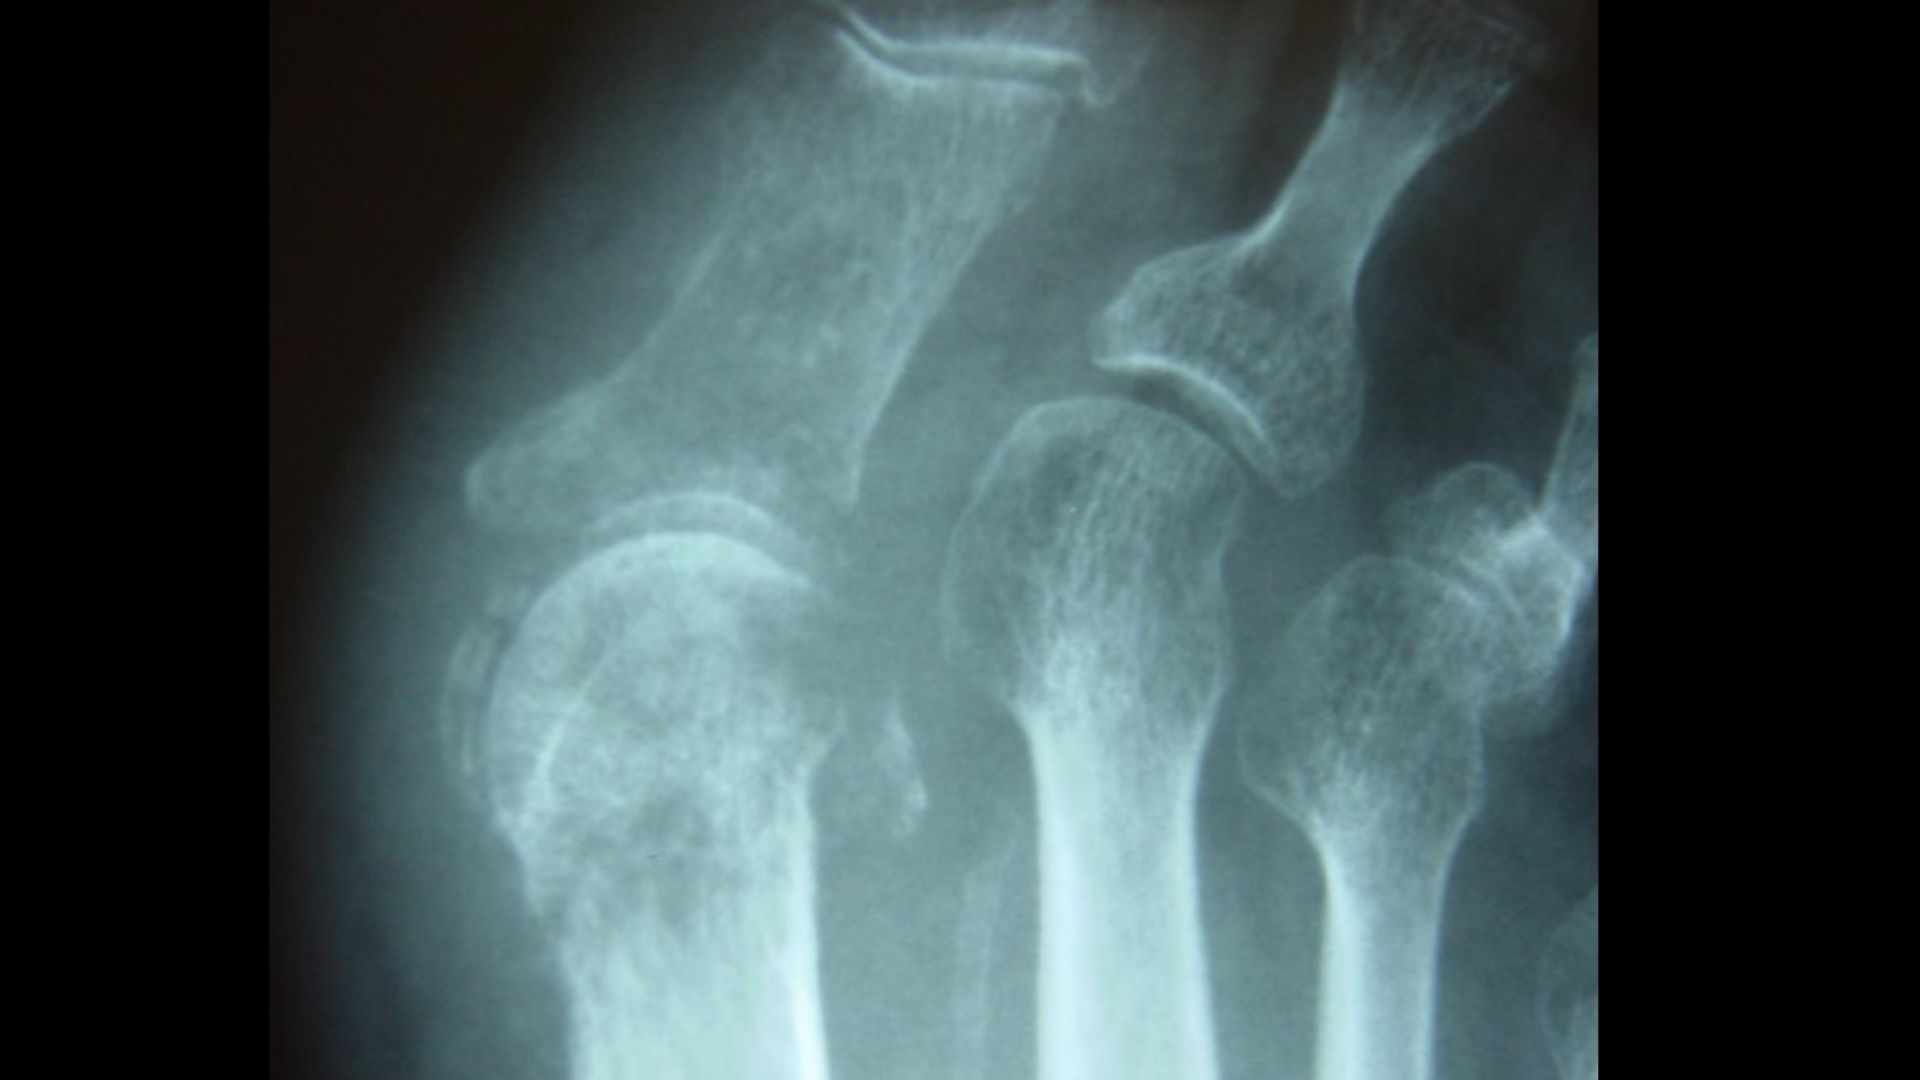

Infección en el hueso. Radiografía del pie de un paciente diabético

Xray mostrando la osteomielitis en el pie en una mujer diabética Pie Diabetico Osteomielitis Diabetic foot infections (dfis) typically begin in a. La amputación del pie o de la pierna se produce fundamentalmente por eventos relacionados con la isquemia o la infección, siendo esta última la causa principal 4. En la presente revisión se. Destruction of the base of 5th. La consecuencia más grave es la amputación 1. Diabetic foot osteomyelitis (dfo) is the. Pie Diabetico Osteomielitis.

Infección en el hueso. Radiografía del pie de un paciente diabético Pie Diabetico Osteomielitis Diabetic foot infections (dfis) typically begin in a. La consecuencia más grave es la amputación 1. Foot infections are a common and serious problem in persons with diabetes. Destruction of the base of 5th. La amputación del pie o de la pierna se produce fundamentalmente por eventos relacionados con la isquemia o la infección, siendo esta última la causa principal. Pie Diabetico Osteomielitis.